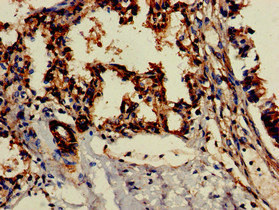

Immunohistochemistry of paraffin-embedded human lung tissue using CSB-PA873604LA01HU at dilution of 1:100

Immunohistochemistry of paraffin-embedded human lymph node tissue using CSB-PA873604LA01HU at dilution of 1:100